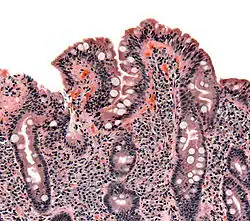

| The ileocecal valve prevents reflux of bacteria from the colon into the small bowel. Resection of the valve can lead to bacterial overgrowth. | |

Finally, abnormal connections between the bacteria-rich colon and the small bowel can increase the bacterial load in the small bowel. Patients with Crohn's disease or other diseases of the ileum may require surgery that removes the ileocecal valve connecting the small and large bowel; this leads to an increased reflux of bacteria into the small bowel. After bariatric surgery for obesity, connections between the stomach and the ileum can be formed, which may increase bacterial load in the small bowel.[21]